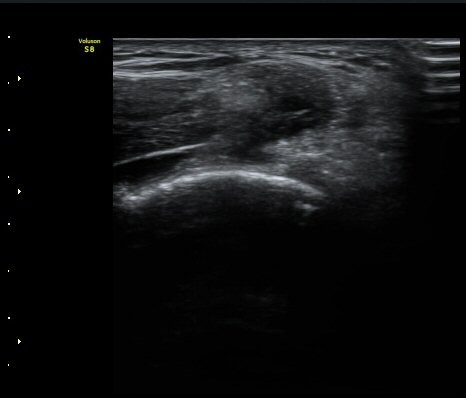

ÃÊÀ½ÆÄ °Ë»ç

³»»ó°ú¿¡¼­ ¼Õ¸ñ±¼°î°Ç Á¾´Ü¸é°Ë»ç»ó ³»¤µ¾Æ°ú ÇÇÁú°ñÀÇ ºÒ±ÔÄ¢º¯È­¿Í ÈûÁÙ³» ¿¬°á¼º

¼Ò½Ç ¹× Àü¹ÝÀûÀÎ Àú¿¡ÄÚ ºÎÁ¾ÀÌ °üÂûµÈ´Ù(±×¸² 1, 2, 3). ±¼°î°Ç ÀϺδ Á¤»óÀûÀÎ °í¿¡ÄÚ

¼¶À¯ ¾ç»óÀ¸·Î °üÂûµÈ´Ù(±×¸² 4). ÈûÁ٠Ⱦ´Ü¸é °Ë»ç¿¡¼­µµ °Ç³» ¿¬°á¼º ¼Ò½Ç°ú Àú¿¡ÄÚ

º¯È­°¡ °üÂûµÈ´Ù(±×¸² 5).  ÃÊÀ½ÆÄÀ¯µµÇÏ ÁÖ»ç ½Ã ÁÖ»ç¾×ÀÌ °Ç³»¿¡¼­ ÀÚÀ¯·Ó°Ô ÆÛÁ®¼­

°ÇÀÇ ½ÉÇÑ ÆÄ¿­À» º¸¿©ÁØ´Ù(÷ºÎ ÆÄÀÏ µ¿¿µ»ó 1).